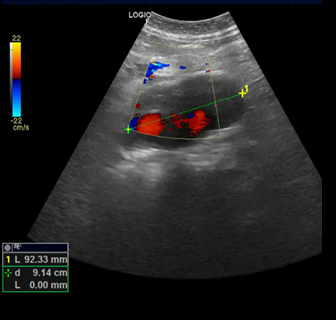

Exploramos con sonda convex en corte longitudinal en epigastrio una imagen ovalada de predominio anecoico de bordes bien delimitados que en corte transverso se extiende longitudinalmente por la linea media de forma ovalada y de diametro mayor a 93,3 mm que presenta contenido hipoecoico en semiluna adherido a pared altamente sugerente de aneurisma aortico con trombo endomural que en algunas zonas ocupa más del 50% de la luz del vaso.